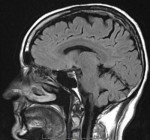

I woke up one morning in the middle of May with a weird headache. Whenever I bent down or stood up, coughed or sneezed, I'd be seized with a sudden pain between the eyes. A couple of sneezes and it would hang on as a dull ache for the rest of the day. I quickly began dreading that familiar tickle ... Continue reading